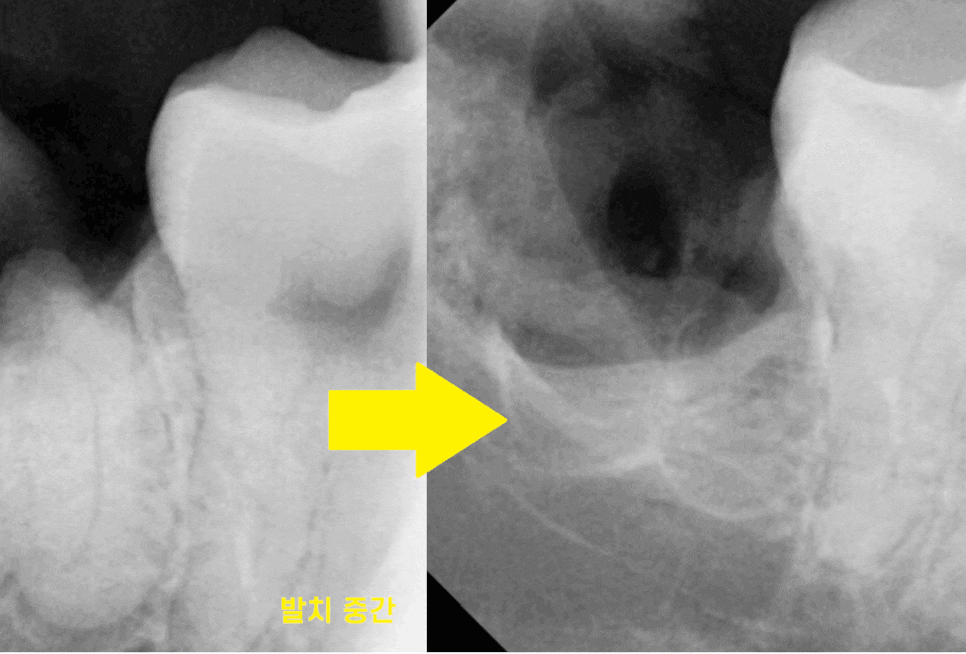

23.07.10

신경과 근접해 있기 때문에

최대한 조심스럽게

치아를 조각내 문제없이

깨끗하게 뽑아드렸습니다.